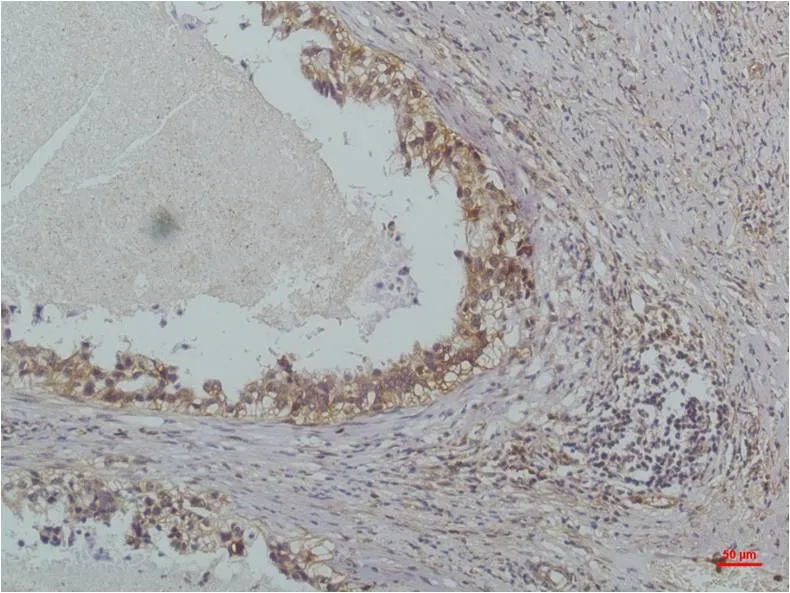

IL-8 (3A4) Mouse Monoclonal Antibody

Cat: AMM00739

Application:IHC-P

Reactivity:Human,Rat,Mouse

Conjugate:Unconjugated

Gene Name:CXCL8